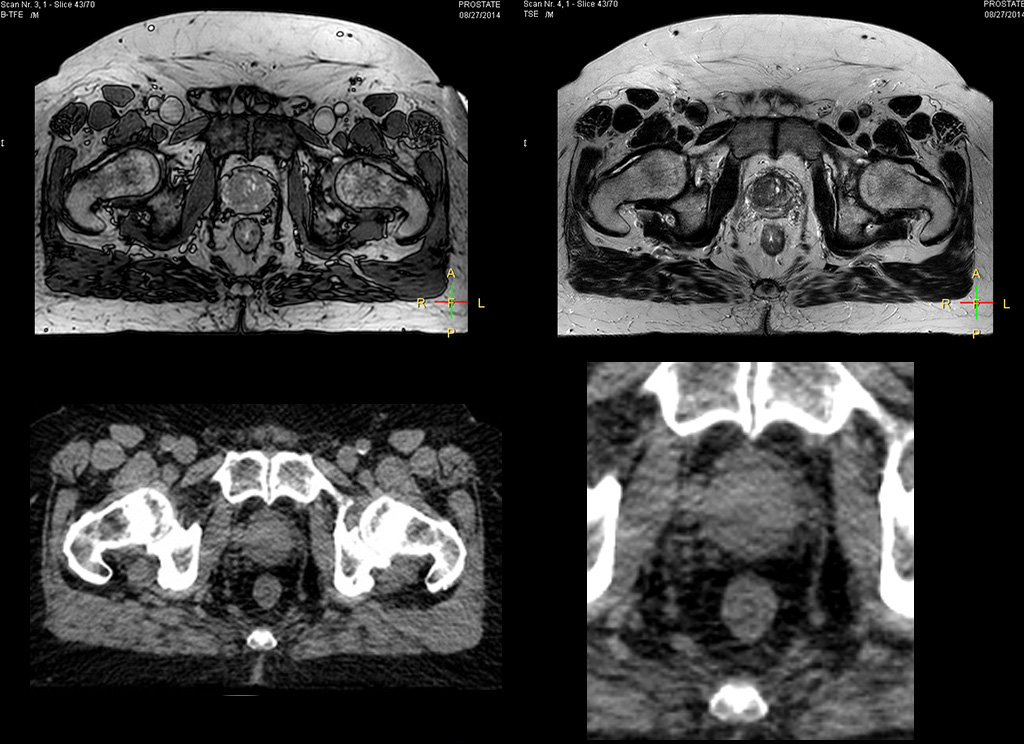

Impressive clinical benefits for prostate

“The biggest problem for CT-based planning, especially in prostate, is you can’t see the cancer very well,” says Dr. Stevens. “On CT it can be quite challenging to see the edge of the prostate especially at the apex. When the edge of the prostate can’t be delineated well on CT, radiation oncologists will increase their margins a little bit so they don’t miss it, but that can also increase toxicity.”

“Using MR, the prostate is well delineated. We quickly see the edges of cancerous tumors like in prostate cancer, and as normal structures can be defined, we can optimize the treatment plan to protect these organs and their normal function. This can potentially improve the outcome. And it improves workflow as well. We can contour more quickly, confident that the tumor is going to be in the field.”

“When a patient registers, first CT simulation and MR simulation are done, followed by CT-MR registration on Pinnacle3. Then the target and normal organ delineation is performed on MR images. Meanwhile we create a reference CT image for online treatment and localization correction. During the treatment phase we can perform additional MRI scans to visualize the anatomy changes and create an adaptive plan. This plan basically adapts the treatment plan to the changes.”